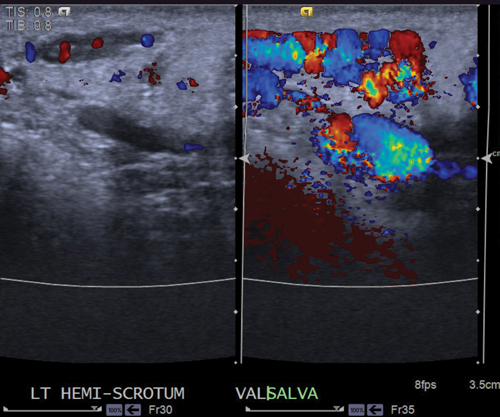

If a varicocele is present, the vessels will enlarge and should demonstrate reversal of flow (Figure 2).

Figure 2: Colour Doppler ultrasound at rest shows dilated vessels, which show reversal of flow

and marked enlargement when the patient performs the Valsalva manoeuvre.